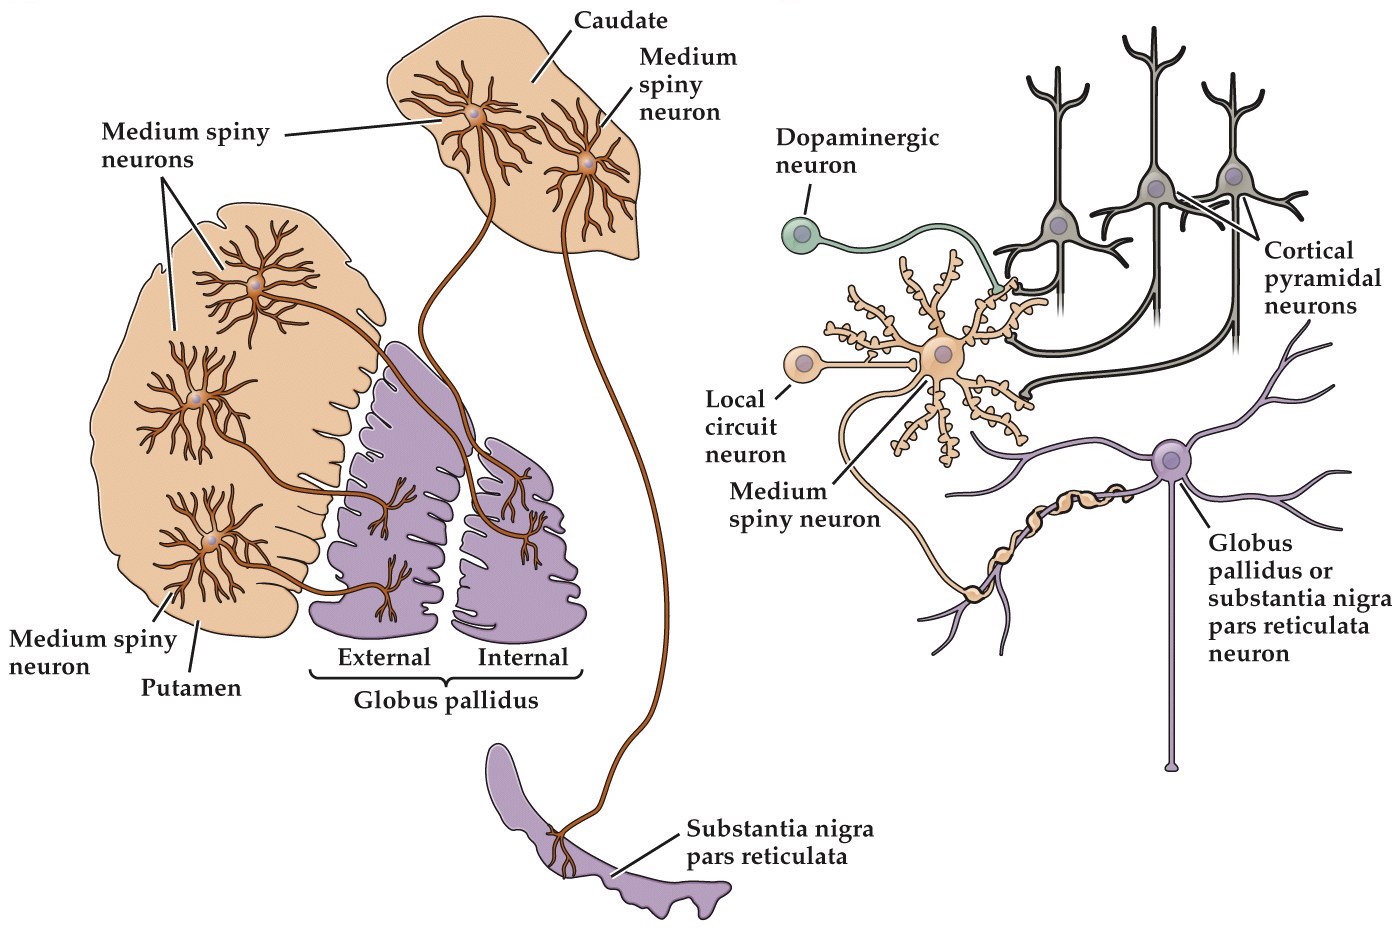

Striatum: medium spiny neurons

- Medium spiny neurons (MSNs) located in caudate and putamen

- ~90% of neurons in striatum. Project to globus pallidus

- GABAergic, inhibitory

- Very little spontaneous activity. Dependent on excitatory input for discharge

- Large dendritic trees

Projections from MSNs

- MSNs of caudate and putamen give rise to inhibitory GABAergic projections that terminate in a pair of nuclei within the basal ganglia called the globus pallidus (GP) and a region of the substantia nigra called the pars reticulata (SNr)

- Approximately 100 MSNs converge onto each neuron in the globus pallidus

- Globus pallidus contains two nuclei– GP externa (GPe) and GP interna (GPi)

- The GPi and the SNr contain the main output neurons of the basal ganglia

- Globus pallidus interna (GPi) neurons then convey information back to the cortex via the thalamus (ventral lateral and ventral anterior nuclei, VA/VL) to make a loop

- Globus pallidus and pars reticulata neurons are GABAergic. Unlike MSNs they have high levels of spontaneous activity– they are tonically active

- Thus the output from the basal ganglia is normally inhibitory-- tonic inhibition

- When MSNs fire (in anticipation of movement) this inhibits the inhibition (disinhibition) and allows upper motor neurons (in cortex and superior colliculus) to send commands to local circuit and lower motor neurons that initiate movement

- Called the direct pathway

Dopaminergic neurons modulate direct and indirect pathways

- Medium spiny neurons (MSNs) in striatum project to the substantia nigra pars compacta (SNc), which in turn projects back to MSNs

- Both MSNs that project to GPe and GPi receive these inputs

- Those that project to GPi have type D1 receptors (coupled to a Gαs, excitatory) and those that project to GPe use type D2 receptors (Gαi, inhibitory)

- Dopamine excites the direct and inhibits the indirect pathway